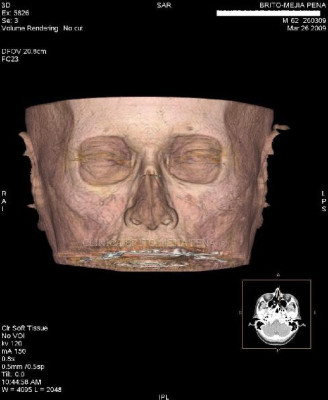

Envíado por BMP Imágenes Diagnósticas

BMP Imágenes Diagnósticas